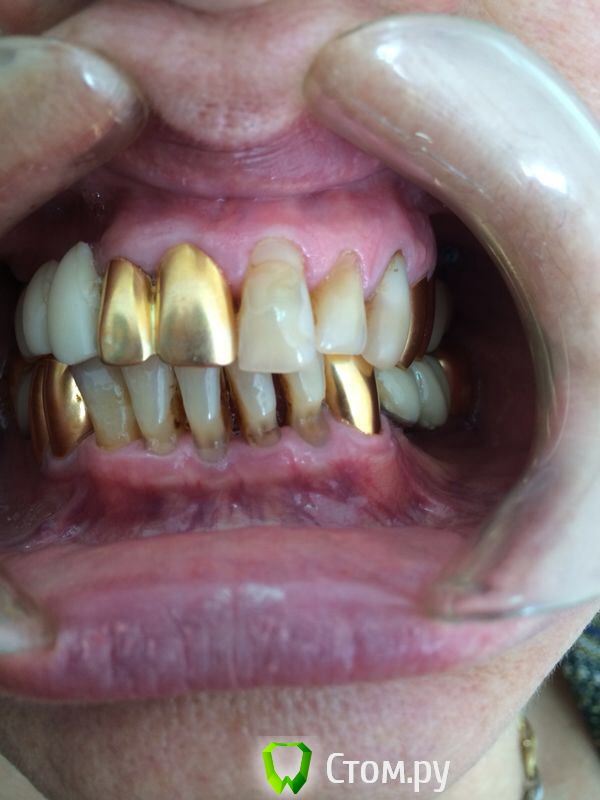

Ислам07 Опубликовано 18 мая, 2014 Поделиться Опубликовано 18 мая, 2014 Уважаемые коллеги подскажите пожалуйста план лечения, меня смущают клиновидные дефекты. Заранее спасибо Ссылка на комментарий

chernov Опубликовано 19 мая, 2014 Поделиться Опубликовано 19 мая, 2014 Уважаемые коллеги подскажите пожалуйста план лечения, меня смущают клиновидные дефекты.Клиновидные дефекты(абфракции)признак перегрузки зубов,т.е. о мостовидных протезах (без имплантации) лучше не задумываться-себе дороже. Ссылка на комментарий